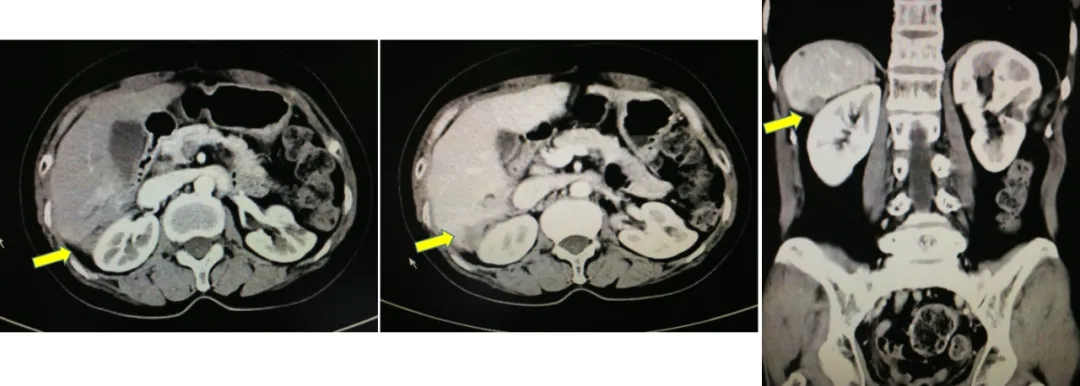

2017-10-26当地查CA125水平为46.3U/ml,2017-12-4我院查CA12水平为110.9U/ml,CT显示肝肾间隙及右肝包膜下片状影较前增大,考虑疾病复发。

CT检查结果

2019.5.8查CA125为78.3U/ml,CT显示右肝后缘欠光整伴片状低密度影。基因检测BRCA1致病性突变,诊断为铂敏感复发卵巢癌。2019.5-2021.4入组BGB-290-102单臂临床研究,口服PARP抑制剂治疗。